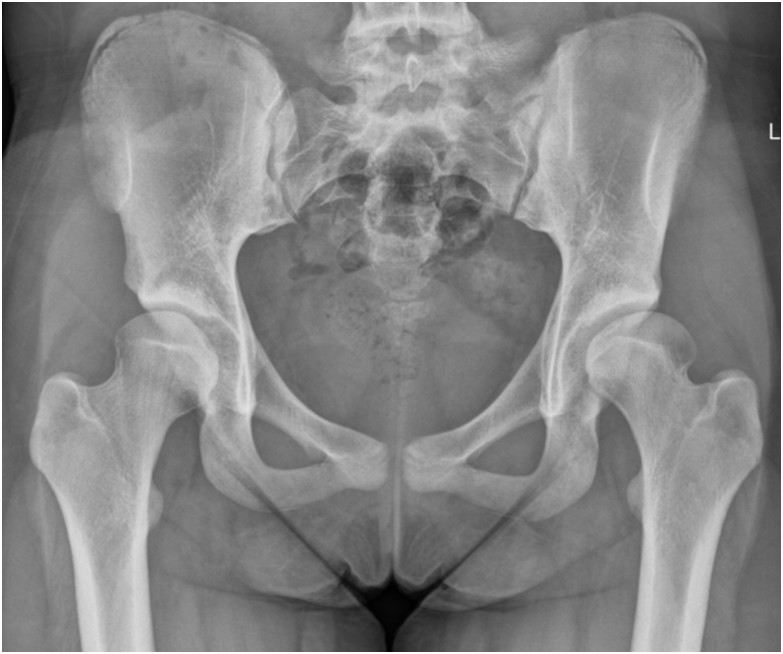

Przedstawiony radiogram wykazuje zmiany zwyrodnieniowe stawu biodrowego powstałe w wyniku:

Pytanie 72